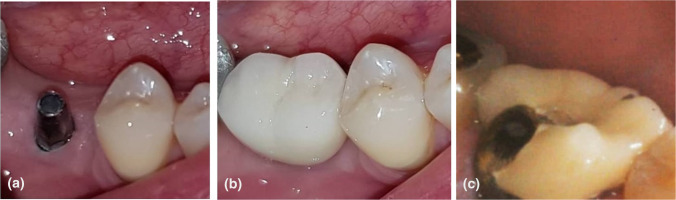

Table 2 presents the frequency of crown detachment and porcelain fracture. There were no significant differences regarding these two variables between the two groups (p > 0.05, Table 2, Fig. 2).

Fig. 2.

Clinical image of the patient who had crown fracture, a before loading, b immediately after loading, c 12 months after loading